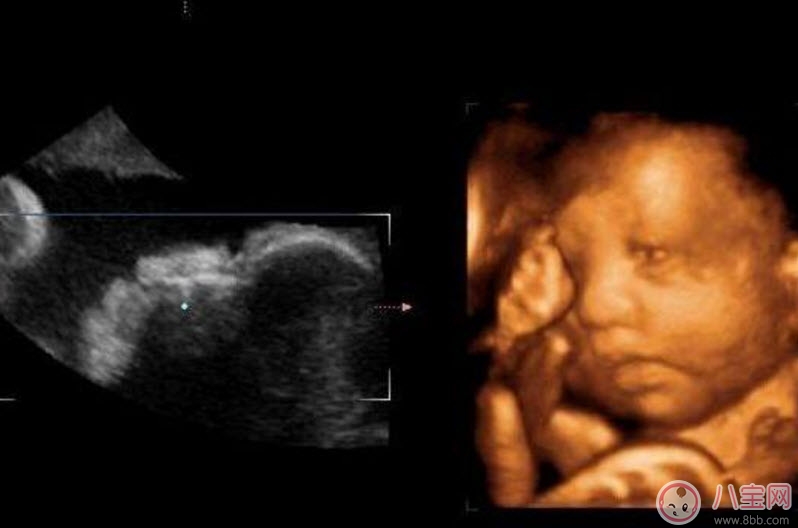

二維超聲可以理解為我們通常說的B超,顯示的是斷面圖像。何為斷面圖像?就是把西瓜切開,你在屏幕上只能看到西瓜的切面(斷面),但經(jīng)驗豐富的你,可以只看這個切面(斷面)就知道這是一個西瓜。

三維、四維超聲就是把很多個二維斷面圖像通過計算機重建成一個立體的圖像。相當于把切成很多片的西瓜,重新堆疊成一個完整的西瓜,這個堆疊過程由計算機完成。三維、四維的區(qū)別在于,三維是照片,四維是影片,四維就是會動的三維照片(實時三維)。

四維彩超的全稱是四維彩色超聲診斷儀,是世界上最先進的彩色超聲設備。四維彩超能夠表面成像,可以更佳清晰的查出來胎兒的四肢發(fā)育是否畸形,腦膜膨出,是否唇腭裂、脊柱裂等先天畸形,及早發(fā)現(xiàn)及早的做出解決方案。